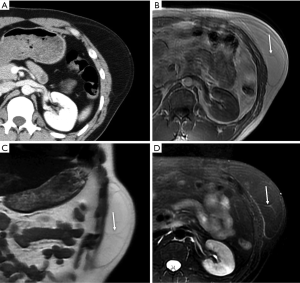

Metastases

Metastases are the most common malignant lesions encountered in the anterior abdominal wall. The imaging characteristics of abdominal wall metastases are nonspecific, but they often resemble the known primary disease in other sites. The single most consistent discriminating feature is the rapid growth of lesions in a known cancer patient, who is usually at an advanced stage and has multiple other metastases. Metastasis of the umbilicus is known as Sister Mary Joseph’s nodule and typically originates from cancers of the gastrointestinal tract and ovary (52-54). The proposed metastasis route of Sister Mary Joseph’s nodule is along with the remnant structures at the umbilicus (55,56). Metastasis to the surgical wound or laparoscopic trocar site and needle-tract seeding after radiofrequency ablation also lead to the formation of abdominal wall metastases (Figure 10). These specific metastases may not be associated with widespread disease in contrast to hematogenous abdominal wall metastases.